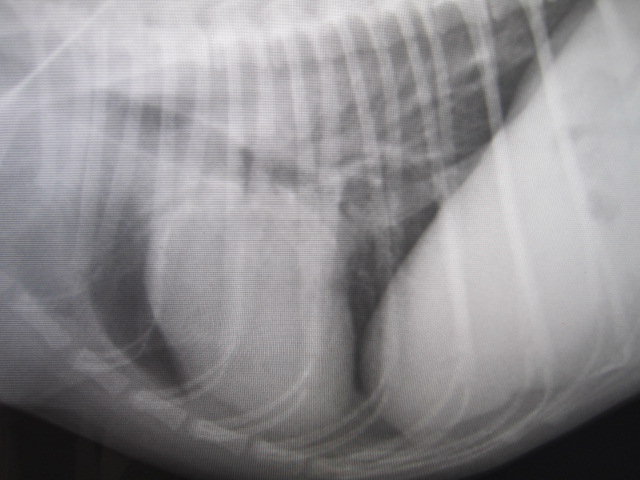

術後のレントゲンです。

食道内の異物はなくなりました。